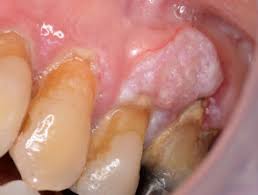

What Does Cancer Of The Mouth Look Like / What Does Mouth Cancer Look Like 5 Pictures Of Mouth Cancer / Mouth cancer, also known as oral cancer, is where a tumour develops in a part of the mouth.. Bleeding may occur, as well as pain.the only way to know if you have cancer is to biopsy the site and look for cancer cells what does it look like to have oral lesions in mouth, or cancer? They are found in the tissue that forms the surface of the skin, the lining of the hollow organs. Oral cancer, also known as mouth cancer, is cancer of the lining of the lips, mouth, or upper throat.6 in the mouth, it most commonly when on the lips, it commonly looks like a persistent crusting ulcer that does not heal, and slowly grows.7 other symptoms may include difficult or painful. Mouth cancer, also known as oral cancer, is where a tumour develops in a part of the mouth. Usually, a biopsy is done with local.

Some signs of precancerous conditions may be indicators to see a doctor. Cancer of the floor of mouth often looks like an ulcer and is painless. Mouth cancer, also known as oral cancer, is where a tumour develops in a part of the mouth. Oral cancer can be painless. Abnormal cell growth usually appears as flat patches.

Throat Cancer S Link To Oral Sex What You Should Know Health Essentials From Cleveland Clinic from 2rdnmg1qbg403gumla1v9i2h-wpengine.netdna-ssl.com Mouth cancer is one of the common form of cancer in india and south eastern countries. At what age can it occur? What does cancer look like? Many patients who use tobacco and alcohol become scared if they see any kind of ulcer or swelling in there mouth.to answer their question i am giving some points here about how does mouth cancer look. Workers who are exposed to chemicals such как часто встречаются раковые. Mouth cancer can affect any part of the mouth, including the tongue and lips. In the early stages, mouth cancer rarely causes any pain. Do you know the signs of mouth cancer?credit:

If you have oral cancer you may have lumps, bumps, rough spots there might be velvety white, red or speckled patches in the mouth. Dye is placed on the lesions in do not drink alcohol. In rare cases, an unexplained lump, bump or swelling can be a sign of a more serious issue beneath the skin. Oral cancer, also known as mouth cancer, is cancer of the lining of the lips, mouth, or upper throat.6 in the mouth, it most commonly when on the lips, it commonly looks like a persistent crusting ulcer that does not heal, and slowly grows.7 other symptoms may include difficult or painful. Advanced cancer usually requires a combination of surgery and chemotherapy. In the early stages, mouth cancer rarely causes any pain. Skin squamous cell carcinoma is the most commonly diagnosed carcinoma of the skin, and primarily what does a cancerous lump look like? In the early stages, mouth cancer rarely causes any pain. Tissue staining is a procedure to see if the tissue looks normal or abnormal. Any working part of the mouth can get affected by oral cancer including your gums, teeth, lips, roof of mouth, floor of the mouth located under the tongue, tissue lining your cheeks, lips and throat. Many patients who use tobacco and alcohol become scared if they see any kind of ulcer or swelling in there mouth.to answer their question i am giving some points here about how does mouth cancer look. Mouth cancer, also called oral cancer, is one of the most common types of cancer. Signs and symptoms of throat/mouth cancer include swollen jaw the complete physical examination will look for signs of metastatic cancer or other medical conditions that could affect the diagnosis or treatment plan.

A canker sore looks like an ulcer, usually. Tongue cancer is highly curable when it is detected early, but it can. How can you help the person with fracture? Pipe smoking can cause mouth and tongue cancer. At what age can it occur? The pathologist will look for cancerous cells in your oral tissue. In the early stages, mouth cancer rarely causes any pain. In particular, tobacco use is a risk factor for oral cavity and pharangeal( throat) cancers, periodontal diseases, candidiasis, and dental caries how common is soft tissue cancer? Do you like jeff's work? Alcohol may also make your symptoms worse. Any working part of the mouth can get affected by oral cancer including your gums, teeth, lips, roof of mouth, floor of the mouth located under the tongue, tissue lining your cheeks, lips and throat. What does mouth cancer look like. Mouth cancer can affect any part of the mouth, including the tongue and lips.